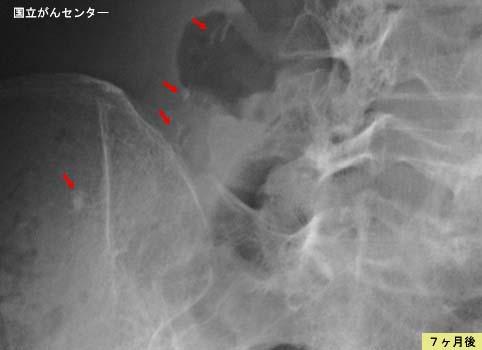

Progreso de la lesión con el paso del tiempo en el seguimiento de Colitis tipo venoesclerosante

Enfermedad Inflamatoria - Ulcerativa/Colitis venoesclerosante

Rayos X